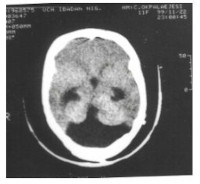

Hydrocephalus literally defined as "water in the head", is not a disease entity but a pathologic condition in which there is enlarged cerebral ventricles unrelated to cerebral atrophy or dysgenesis. It results from imbalance of production and absorption of cerebro-spinal fluid (CSF) or obstruction to the passage of CSF between its origin and point of absorption'. There are various causes of hydrocephalus which could be congenital or acquired. The Dandy-Walker syndrome may be defined as a developmental anomaly of the fourth ventricle and cerebellum in which the foramen of Magendie is atretic with or without associated atresia of one or both foramina of Luschka thus resulting in obstructive hydrocephalus The incidence of the Dandy Walker syndrome in hydrocephalic patients is quite rare; most of the patients were under the age of two years at the time they presented with symptoms. Below is presented a case of Dandy Walker syndrome who first presented with symptoms of hydrocephalus at the age of eleven years.